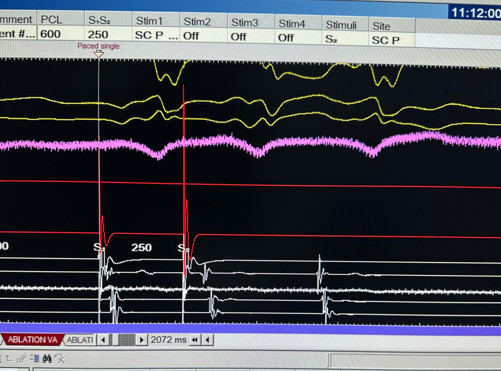

The patient underwent a cardiac electrophysiological study. Multipolar electrode catheters were advanced into the femoral vein and positioned in the right atrium, His-recording region, right ventricular apex, and coronary sinus. Retrograde conduction was existed via the atrioventricular (AV) node. Atrial pacing during tachycardia revealed AV conduction and a ventricular-atrial response. Figure 4